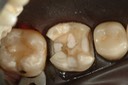

Alan Chinn #2 finish